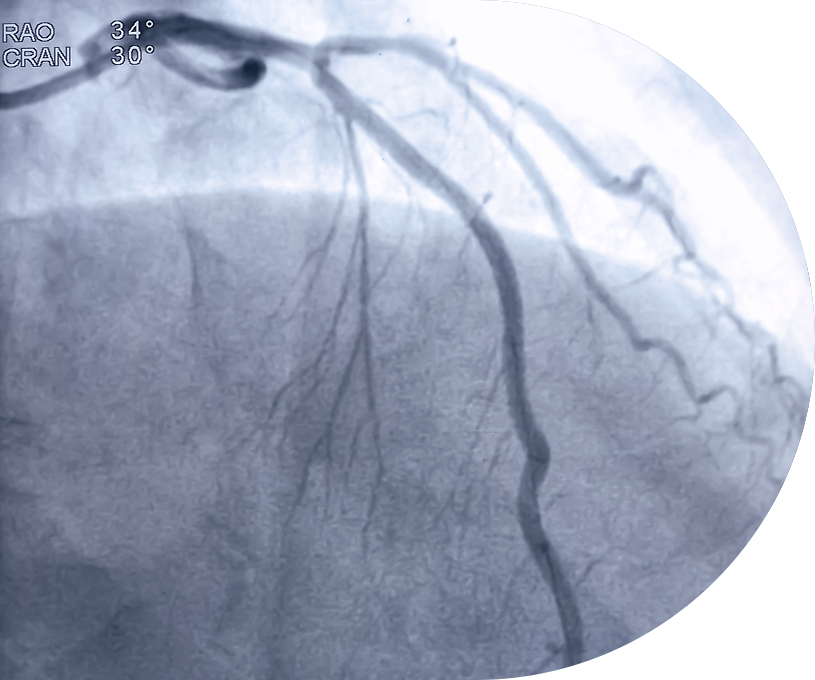

HERZKATHETER-

UNTERSUCHUNG

Bei entsprechender medizinischer Indikation ist durch die enge Kooperation mit der LMU eine zeitnahe Terminierung einer invasiven Herzkatheterdiagnostik möglich.

Die Untersuchung dient der genauen Darstellung der Herzkranzgefäße und ermöglicht bei Bedarf unmittelbar therapeutische Maßnahmen, wie beispielsweise eine Stentimplantation.

Ziel ist eine schnelle, leitliniengerechte Abklärung und Behandlung relevanter Herzerkrankungen.